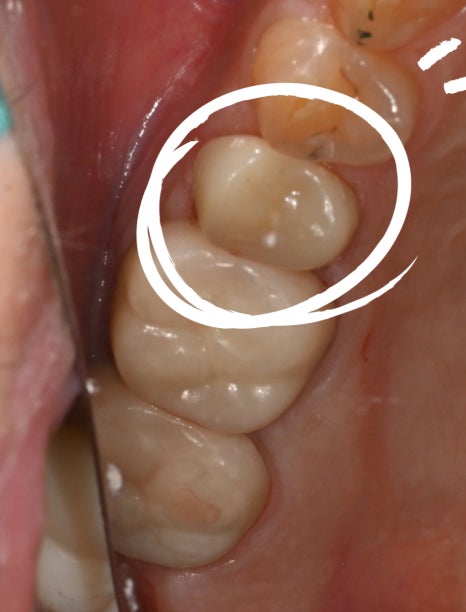

<Before treatment / After treatment>

And because molars are areas that receive a lot of force,

after root canal treatment they must be protected by covering them with a crown.

The final step is a strong finish with a zirconia crown

Once the root canal treatment is complete, the final step is

to finish with a zirconia crown.

Zirconia is highly durable,

long-lasting, resistant to breaking,

and has a natural color,

so it is a material that fits molars very well.

Once the crown is placed like this,

even when a molar breaks,

its function can be restored almost to how it was originally.